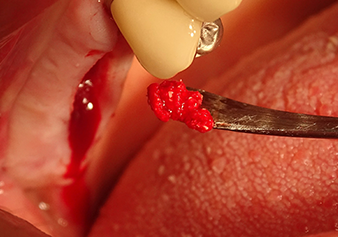

После промежуточного контроля (рис. 4) был проведен еще один этап подготовки (рис. 5). За тем, с помощью гидравлического инструмента Z35P мембрана была поднята в нужное положение (рис. 6 и 7). Далее, следовала дальнейшая пьезохирургическая подготовка ложа для имплантата, завершенная с помощью ротационного бора и лопаточной фрезы до диаметра имплантата 4,8 мм. Перед установкой имплантата под мембрану Шнейдера был введен аугментационный материал (размер частиц около 0,8-1,6 мм) (рис. 8).

A periosteal elevator is used to place an augmentative mixture carefully into the region of the internal maxillary sinus ostium in the apical direction

Рис.8: Используя периостальный лифт, в область внутреннего остия верхнечелюстной пазухи в вертикальном направлении осторожно помещается аугментационная масса.